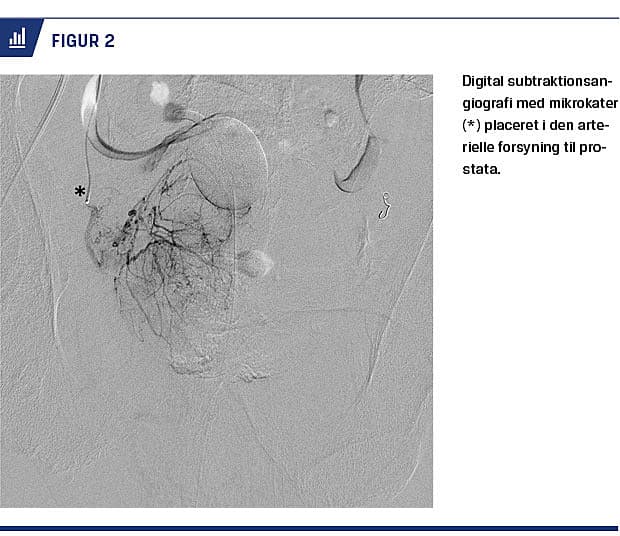

Arteriel adgang etableres ved punktur af arteria femoralis communis og anlæggelse af et indføringshylster, som herefter fungerer som adgangsport for kateterfremførelse (Seldingers teknik). Ved vanskeligt fremkommelig anatomi kan det være nødvendigt med punktur på begge sider, og alternativt kan en arterie i armen benyttes [19]. Digital subtraktionsangiografi (DSA) er en teknik, som gør det muligt kun at fremstille kontraststoffordelingen, og dermed visualiseres karanatomien i bækkenet. Ved hjælp af kontrastindsprøjtning og DSA styres guidewiren, og begge prostataarterier kateteriseres med et tyndt og fleksibelt kateter (Figur 2). Orientering gøres nemmere ved anlæggelse af et blærekateter med kontrastfyldt ballon, der virker som pejlemærke. Inden der administreres partikler, udføres der en cone-beam-CT (CBCT). Ved en CBCT fremstilles en tredimensional rekonstruktion af anatomien under kontrastindgift, hvilket sikrer korrekt kateterplacering i den arterielle forsyning til prostata uden forbindelse til de omkringliggende organer, herunder blære, rectum og penis [20]. Herefter kan prostataarterierne selektivt okkluderes ved håndinjicering af emboliseringspartikler. Der anbefales bilateral embolisering, som har en bedre effekt end en unilateral procedure, selvom unilateral embolisering medfører reduktion i symptomerne hos næsten halvdelen af patienterne [6]. Præoperativt gives der rutinemæssigt antibiotika intravenøst.